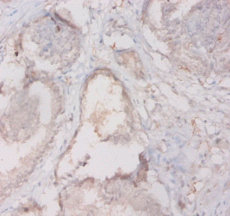

ApplicationELISA, IHC; Recommended dilution: IHC:1:10-1:100